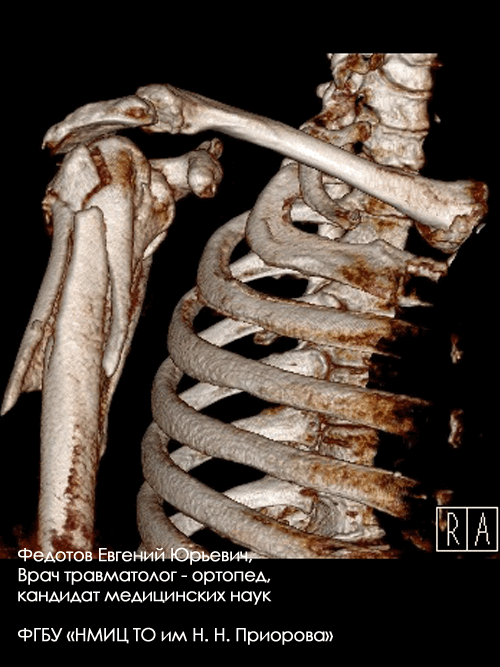

Закрытый многооскольчатый внутрисуставный со смещением перелом проксимального отдела плечевой кости.

Операция: открытая репозиция отломков проксимального отдела плечевой кости, накостный остеосинтез пластиной и винтами